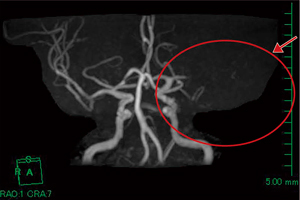

図4 頭部MRA:脳梗塞症例(図3と同一症例) |

脳腫瘍や脳卒中などの虚血性疾患においてASLの有用性は高いが,位置関係の把握が困難な場合も見受けられる。そこでASLデータ中のperfusion imageデータとT2強調画像をfusionさせることにより,位置関係をより正確に描出することが可能である(図1〜4)。

頭部MRIにおける当院ルーチン撮像は,MRA,FLAIR,T1強調画像,T2強調画像,拡散強調画像,3D ASLを行っている。基本断面は横断像であるが,冠状断・矢状断像も適時追加撮像を行っている。